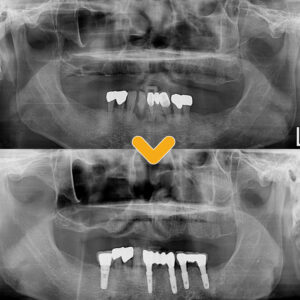

18. 수암동치과 틀니와 임플란트를 같이 할 수도 있나요?

수암동치과 틀니와 임플란트를 같이 할 수도 있나요? 안녕하세요. 모든 진료에 진심을 다하는 곳, 더플러스치과입니다. ​ 다수의 치아를 상실하였을 경우 임플란트나 틀니 등을 이용하여 상실된 부위를 대체하게 되는데 특히 고령의 어르신분들이나 약을 복용 중인 전신 질환자, 경제적인 부분이 부담되시는 분들의 경우 더보기…